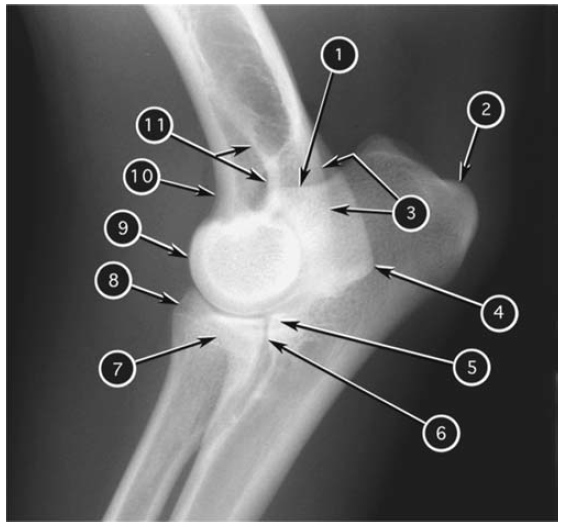

Mediolateral radiograph of canine elbow joint

What number?

- Cranial border of medial epicondyle of humerus

- Cranial border of lateral epicondyle of humerus

- Caudal border of medial epicondyle of humerus

- Caudal border of lateral epicondyle of humerus

- Condyle of humerus

- Anconeal process of ulna

- Tuber olecrani of ulna

- Medial coronoid process of ulna

- Lateral coronoid process of ulna

- Proximal radioulnar joint

- Head of radius

A

1. Anconeal process of ulna

2. Tuber olecrani of ulna

3. Caudal border of lateral epicondyle of humerus

4. Caudal border of medial epicondyle of humerus

5. Lateral coronoid process of ulna

6. Proximal radioulnar joint

7. Medial coronoid process of ulna

8. Head of radius

9. Condyle of humerus

10. Cranial border of medial epicondyle of humerus

11. Cranial border of lateral epicondyle of humerus